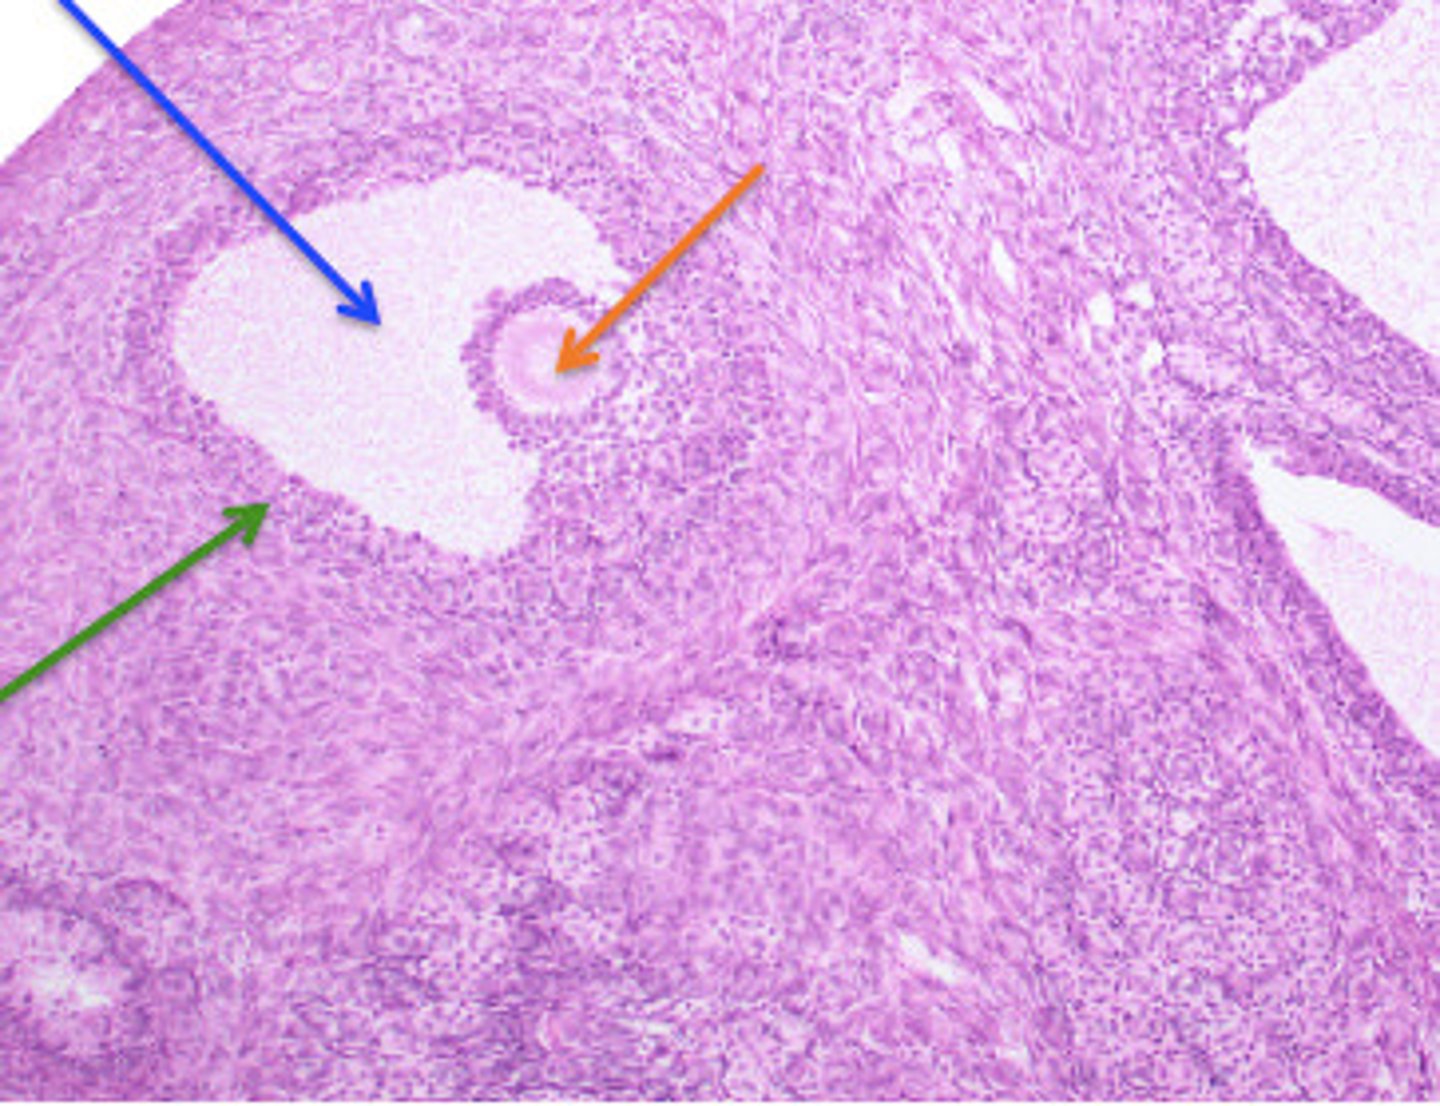

Ovary: Progesterone/Estrogen, Inhibin, Relaxin

Name this organ and hormones produced here

Mature Follicle

Blue arrow (general structure)

Oocyte

orange arrow

Follicle Cells

green arrow